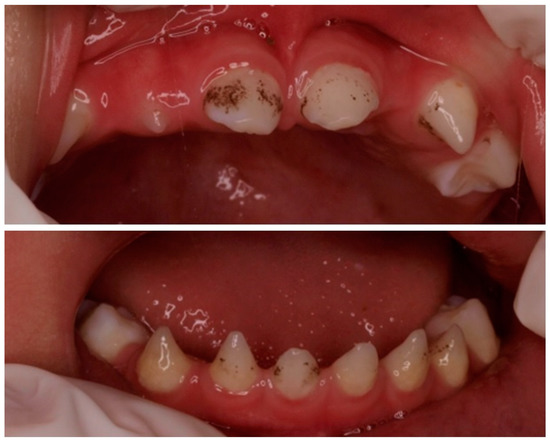

Figure 1.

Presence of conical anterior temporary teeth. Absence of the left lateral maxillary incisor and the maxillary and mandibular second molars.

We present the case of an 11-year-old Chinese boy who was referred to the dentist at the age of 23 months. In the first visit, it was noted that the boy was missing the left maxillary lateral incisor (6.2) and the maxillary and mandibular second molars (5.5, 6.5, 7.5, 8.5) and that he had conical-shaped anterior teeth (5.2, 7.2, 7.1, 8.1, 8.2) (Figure 1). The clinical examination results of his hair, eyes, eyebrows, nails, fingers, and skin were normal, except for dryness of the skin. His weight and height were at the 10th percentile. According to the parents, dental eruption was age-appropriate, at around 6 months of age. Psychomotor development was normal, and there were no previous episodes of fever or other significant pathologies. He was born at term after an uncomplicated pregnancy. The parents were nonconsanguineous. The paternal grandparents came from Daxue, China, and the maternal grandparents from Yuhu Village, China. The paternal grandparents came from Daxue, China, and the maternal grandparents from Yuhu Village, China.